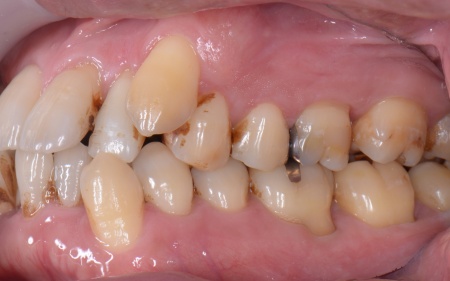

| カウンセリング | 拝見したところ、上下の歯は、ずれたりねじれたりしてデコボコに生えており、著しく歯並びが乱れていました。

またレントゲン撮影をして確認すると、右上前歯は顎の骨の中に埋まっている骨性埋伏(こっせいまいふく)の状態でした。 さらに、左下奥歯は重度の歯周病であり、歯を支えている骨が一部溶けていることが判明しました。 以上のことから、歯並びを整える矯正治療と歯周病の治療を併せて行う必要があると診断しました。 |